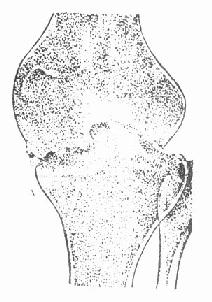

初起时大多为滑膜型,骨型病灶多在胫骨上端或股骨下端,均可扩散为全关节结核(图3-222)。滑膜肥厚充血,颜色稍灰暗,呈半透明状,有的部分显示豆渣或豆腐乳样,可有积液和粘连,肉芽组织蔓至软骨面上,有的可因磨擦力而脱落,露出骨面。如骨骺破坏,可引起肢体短缩畸形。由于膝关节周围缺少肌肉覆盖,肌肉萎缩肿胀明显,关节呈梭形肿大。脓肿较易穿破形成窦道,病程很长,很难自愈,多需手术治疗。

股骨干骺端结核扩散至膝关节

图3-222 股骨干骺端结核扩散至膝关节 图3-223 膝关节全关节结核,有骨质破坏,关节间隙消失